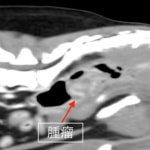

腫瘤が比較的大きい為、早期の外科的切除を提案しました。術前のCT検査にて腫瘤が孤立性であり肺やリンパ節への明らかな転移像がみられないことを確認した後、直腸腫瘤の切除手術を行いました。

CT画像